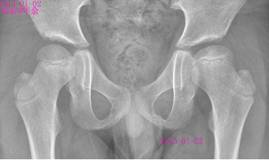

朱××,男,45岁,双侧股骨头坏死,左侧髋关节疼痛明显,不能独立行走,需使用止痛药物(图1,MR)。介入治疗术中造影(图2a)示:股骨头供血动脉分支稀疏,远端痉挛、股骨头骨质内无明显分支动脉血管;治疗后(图2b)造影见股骨头供血动脉分支血管明显增多,远端可见达股骨头骨质内,原髋关节疼痛消失,自行行走出院。

图1 图2a 图2b